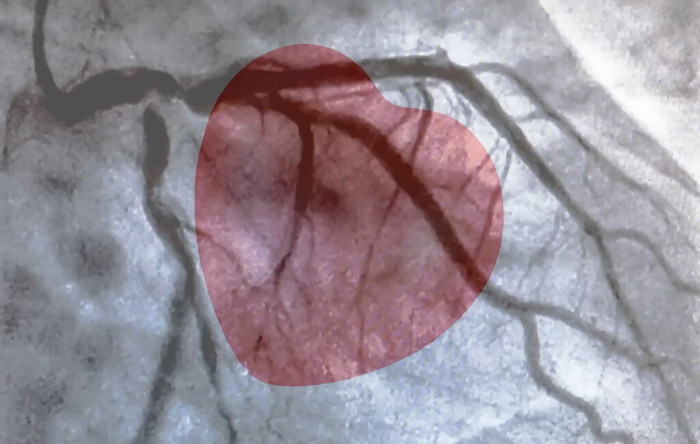

2、心脏CT , 对于有心绞痛发作的人 , 可以在医生评估下 , 决定是否行心脏CT检查看看心血管是否有狭窄 , 或狭窄加重 。

3、心脏造影 , 对于有典型的心绞痛或不明确是否是心肌缺血的情况下 , 在医生指导下 , 可以行冠脉造影检查 , 看心血管狭窄程度 , 看看之前支架的情况等等 。